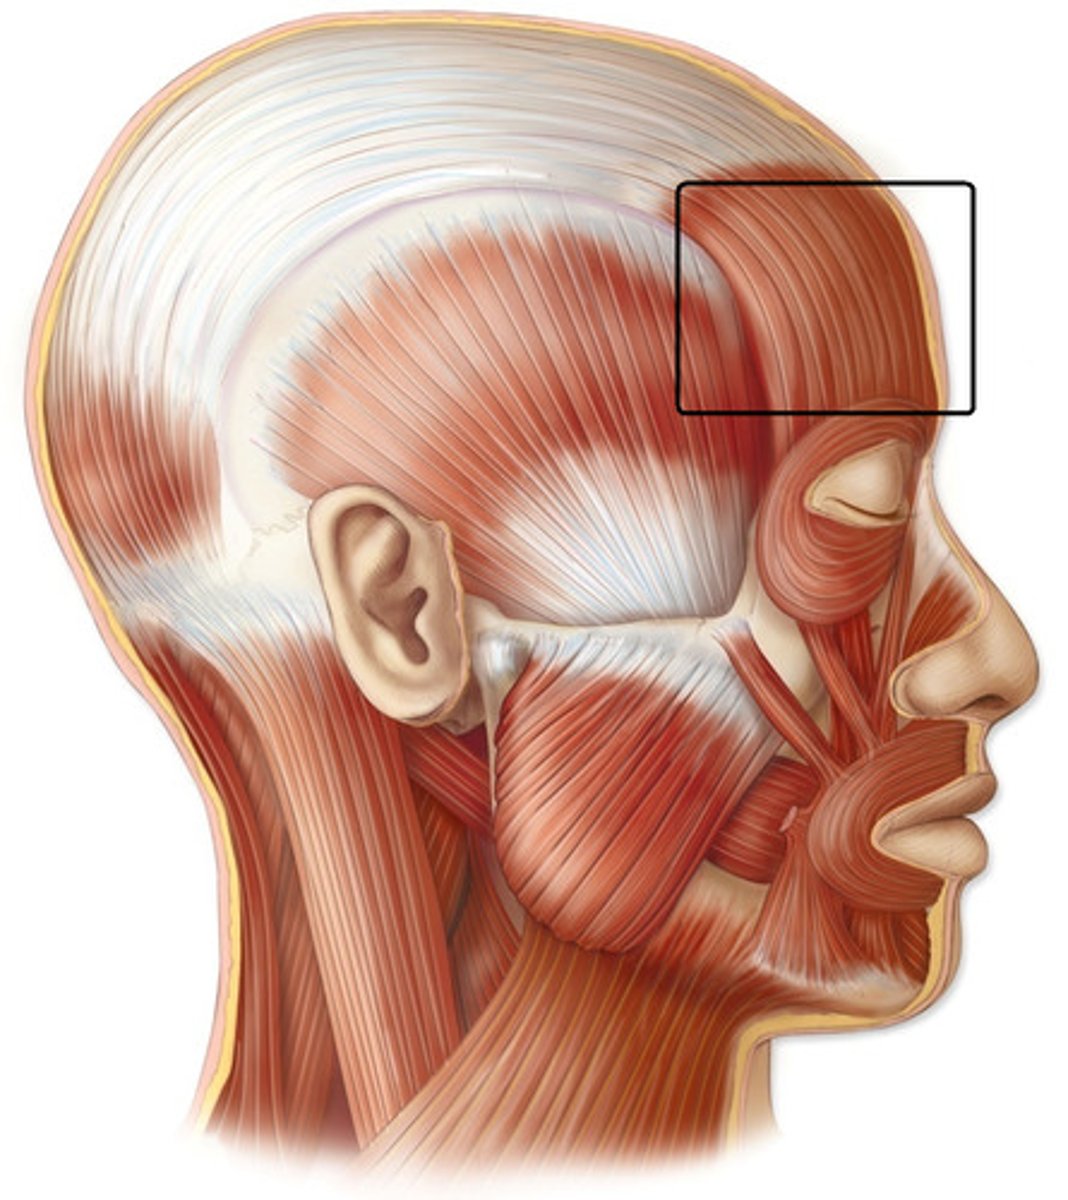

frontalis

elevates eyebrows and scalp